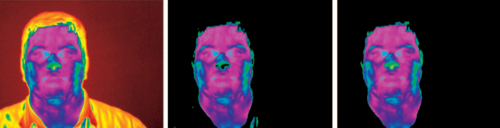

研究提出了一种解决热面部识别问题的新颖方法,该方法可以充分利用热红外波段的潜力。它由统计面部分割和针对热现象学量身定制的生理特征提取算法组成。生理载体由面部血管网络的热烙印形成。预测了从热面部图像提取血管网络并将其用作面部识别的特征空间的可能性。目标是人们对红外热像仪中人脸识别的另一种思考方式,以促进体温快速检测。与其他方式相比,它具有明显的优势。面部热图像由红外热像仪捕获。对于要存储在数据库中的每个主题,记录五个不同的姿势。将两步分割算法应用于每个姿势图像,以从面部提取血管网络。

图为红外热像仪测体温

为了建立可行性,提出了一种使用热成像中包含的生物热信息来捕获面部生理模式的特定方法。该方法的基础是利用特征和时不变的生理信息来构建特征空间。尽管面部热图随时间推移而移动,但浅层脉管系统与周围组织之间的对比度仍保持不变。这种生理特征具有永久性,在皮肤下很难改变。因此,它为可以使用它的任何面部识别方法提供了强大的优势。具体来说,方法如下:首先,使用新颖的贝叶斯分割算法将面部组织与背景分离。其次,通过使用白色大礼帽分割并进行各向异性扩散,从皮肤表面提取血管轮廓网络。第三,将TMP定位在血管网络中,并将其用作特征向量的基础。第四,它通过匹配基于TMP的特征向量来执行识别。从指纹识别中借鉴了一些想法,因为血管网络似乎与神经网络在现象学上相似。